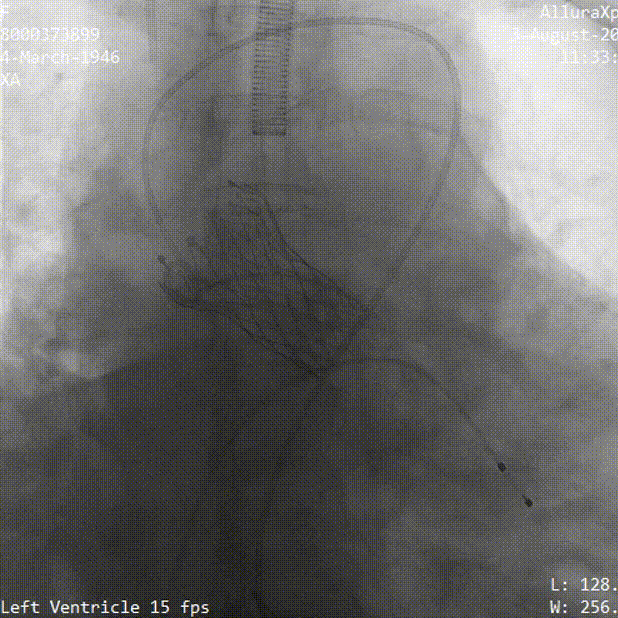

冠脉灌注良好

瓣膜稳定脱钩过程

最终位造影 形态良好 位置理想

无瓣周漏 即刻跨瓣压差为3mmHg